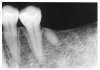

Dentin caries extends into the tooth dentin and can be recognized by noting the focal loss of dentinal radiopacity. Most commonly, this darkened dentin is located beneath carious enamel and, typically, the lateral dimension of the dentinal involvement exceeds that of the associated enamel caries (Figure 3). Dentin caries may be discerned interproximally, on the occlusal surface, buccally/lingually, or on root surfaces.

Figure 3 - Dentin Caries

Figure 3